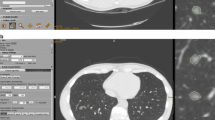

First, semi-automatic measurement of the diameter of SSNs (DSSN) and internal solid portions (Dsolid) were performed by two radiologists (E.J.H. and H.K.) independently, using commercial software (Veolity version 1.2, MeVis Medical Solutions, Bremen, Germany) [13, 15, 16]. Readers initially determined and clicked one of the three nodule types (pure ground-glass, part-solid or solid) based on visual assessment according to Fleischner Society recommendations [2]. Thereafter, users defined a target by dragging a line traversing the nodule on an axial plane. Based on the predefined attenuation threshold for the ground-glass [-750 Hounsfield units (HU)] and solid portion (-350 HU) [15], the software determined the segmentation boundary [17]. Readers were allowed to adjust the segmentation boundary by tuning attenuation thresholds or the roundness of each component (ground-glass and/or solid portion), if necessary. Successful segmentation was evaluated subjectively by each reader (Electronic Supplementary Material 1) and was defined as correct segmentation proportion of 80 % or greater according to previous literature [13, 15, 18]. After segmentation, the effective diameters (diameter of a sphere where the volume equals the nodule volume) of both DSSN and Dsolid were provided. Thus, the nodule type, DSSN and Dsolid assessed by both readers were recorded for the successfully segmented SSNs.

Measurement of the internal solid portion of an invasive pulmonary adenocarcinoma appearing as a subsolid nodule in a 77-year-old male. (a) Manual average diameter of the internal solid portion was measured as 4.7 mm and 7.6 mm by readers 1 and 2, respectively, on an axial plane of a non-enhanced CT scan. (b) Semi-automatic effective diameter of the internal solid portion was 6.6 mm for both readers. The measurement as well as nodule classification was consistent between the two readers. (c) Semi-automatic segmentation boundary was overlaid on the coronal CT image